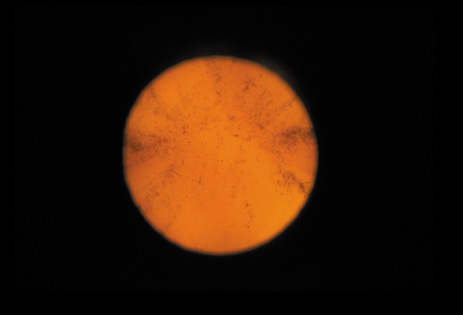

Cortical opacities have been clinically observed to develop earliest in the inferior half of the lens, especially the lower nasal quadrant.28 Epidemiologic29 and laboratory studies30 have suggested that cortical cataracts may be caused by ultraviolet rays from sunlight. The supraorbital margins may block the ultraviolet rays from falling over the upper part of the lens, thus making cortical cataract less frequent in the upper quadrants. Eventually these opacities also develop in the periphery in other quadrants, resulting in a circular array of spokes and peripheral cuneiform opacities (Fig. 9). Bands of central cortical fibers may become prominent and opacify centrally (Fig. 10). However, most cortical cataracts remain in the periphery for many years, even decades, before the central axis of the lens becomes involved, causing loss of vision late in the development of the cataract.

Fig. 9. Moderate cortical changes. Wedge-shaped (cuneiform) or spoke-like (wheel) peripheral changes are seen. These changes may be extensive but may not affect Snellen visual acuity since they occur in the periphery.

This type of cataract is best seen with retroillumination, which gives an enhanced picture of the cortical spokes and vacuoles by the shadows they cast as the light is reflected back by the fundus. Direct illumination helps clarify the level of the opacities (see discussion in the Posterior Subcapsular Cataract section below).